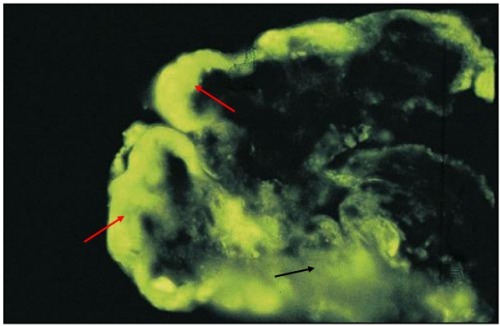

2. 免疫荧光:

图 20 红色箭头:IgG 沿肾小球毛细血管壁沉积;黄色箭头:IgG 沿肾小球系膜区沉积

图 21 红色箭头:IgG 在系膜区沉积;黄色箭头:IgG 在内皮细胞下和毛细血管壁沉积

图 22 红色箭头:IgG 沿肾小球毛细血管壁、内皮下沉积;黄色箭头:IgG 在肾小球系膜区沉积